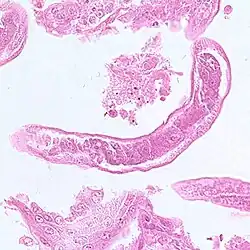

| Capillaria infectie bij een zestienjarig Filipijns meisje | |||||||||||||||

Capillaria philippinensis (synoniem: Paracapillaria philippinensis) is een parasitaire rondworm, die tot het geslacht Capillaria (synoniem: Eucoleus) behoort. De rondworm veroorzaakt intestinale capillariasis bij mensen. De ziekte werd voor het eerst in 1964 waargenomen in het noorden van Luzon, Philippijnen. Er zijn ook gevallen bekend in China, Egypte, Indonesië, Iran, Japan, Korea, Laos, Taiwan en Thailand.[1] Infecties in Italië en Spanje werden waarschijnlijk in het buitenland opgelopen, waarvan een in Colombia.[2] Besmetting ontstaat door het eten van rauwe vis.

Volwassen mannetjes zijn 1,5-3,9 mm lang en 23-28 µm dik. De vrouwtjes zijn 2,3-5,3 mm lang en 29-47 µm dik. De eieren zijn 35-45 µm lang en 20-25 µm breed en hebben een gestreepte buitenwand.

Bacillaire band (blauwe pijl), darm (rode pijl) en uterus met een ei in dwarsdoorsnede (zwarte pijl) -